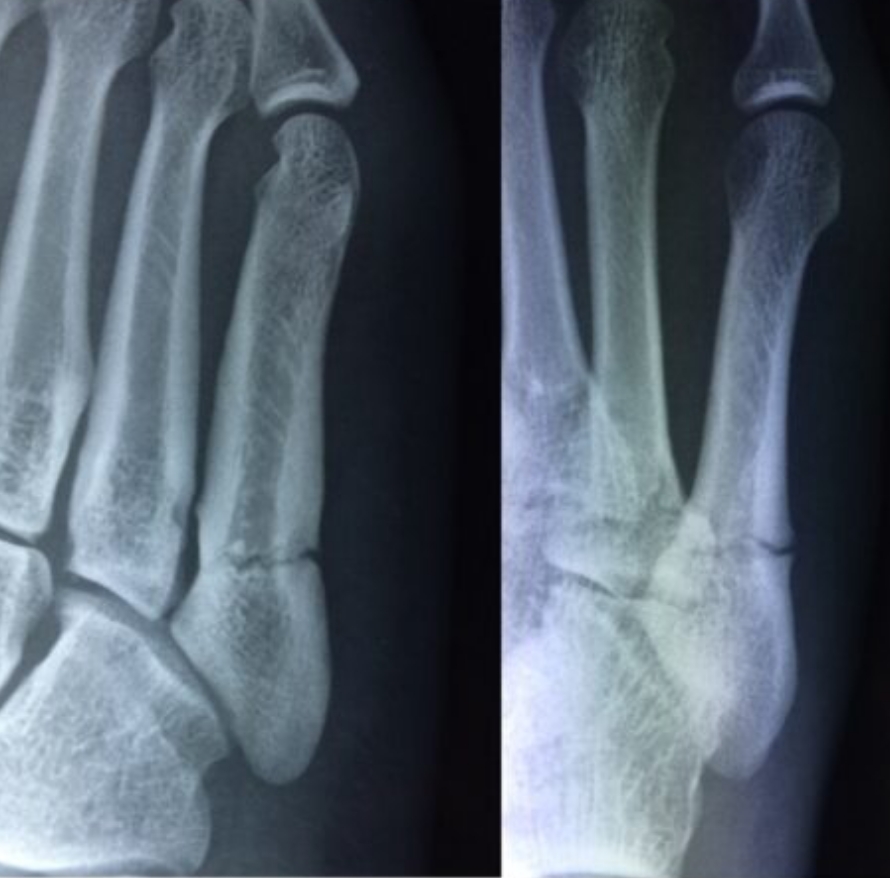

2020-12-09 スポーツ整形 ページ内リンク 第5中足骨骨折(ジョーンズ骨折)【スポーツ整形外科】 第5中足骨骨折(ジョーンズ骨折)【スポーツ整形外科】 サッカーやバスケット等の切り返しの多い競技にしばしば発生する。⇒スクリューによる固定で2〜3か月で復帰。 術前 術後 術後12週間 関連ページ スポーツ整形 一覧へ戻る